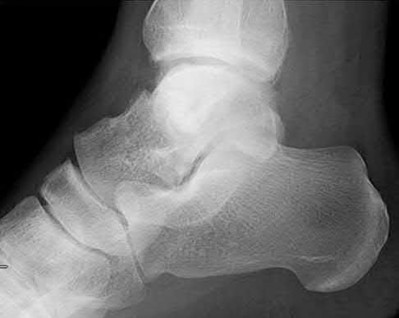

Figure 28 is the lateral radiograph of a patient who sustained an intra-articular fracture of the calcaneus. The structure (*) depicted by the arrows most likely represents which osseous component of the calcaneus?

Lateral portion of the posterior facet Corrent answer: 5

Fractures of the calcaneus occur as a result of shear and compression forces. Foot position at the time of impact, the force of the impact, and bone quality all dictate the degree of comminution and fracture line orientation. Two primary fracture lines are consistently observed, one of which divides the calcaneus into medial and lateral portions. An essential feature of this fracture

line is that it creates a fragment (sustentaculum tali) that remains attached to the talus by the interosseous ligament. This medial portion (constant fragment) of the posterior facet retains its normal anatomic position beneath the posterior talus. Its corresponding lateral component (labeled with an * in the figure), however, can be found displaced inferiorly within the body of the calcaneus. It is often rotated 90 degrees (as depicted in Figure 28) in relation to the remainder of the subtalar joint. This gives the appearance of what has been described as the "double-density" sign. The middle facet is more anterior and less commonly displaced. The lateral wall is nonarticular.